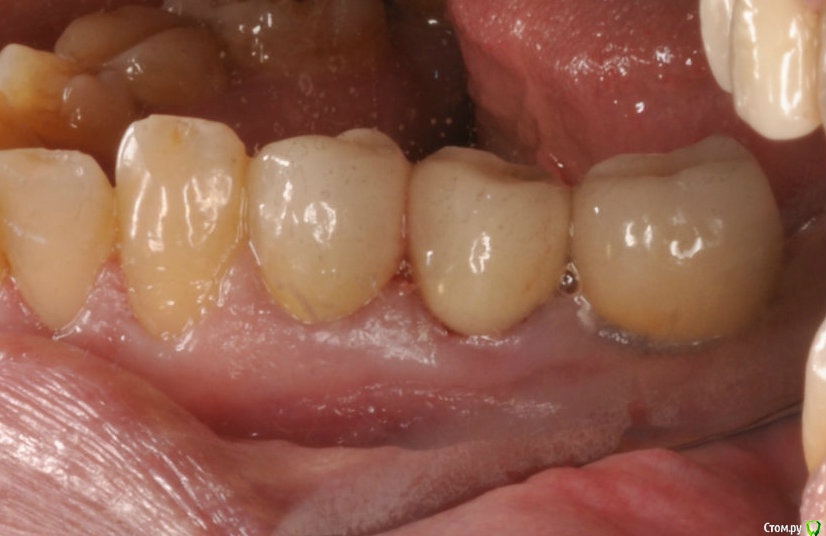

kriokov Опубликовано 1 апреля, 2017 Поделиться Опубликовано 1 апреля, 2017 Ревматоидный и метатрексат.(тоже просил помощи у коллег) Болт в обл 36, суперлайн. фото с коронкой полгода назад ортопед сделалМне кажется свищи, это имплантат коронально "голый ", и слизистая тонкая, хотя всегда возможны другие факторы. 1 Ссылка на комментарий